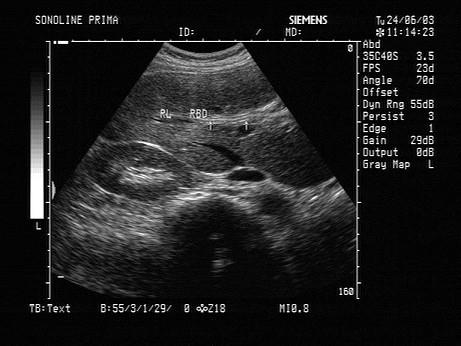

问题 女,34岁,经常反复发作剧烈的右上腹痛,加重1天。声像图如图所示,最可能的诊断为?(?)

选项 A.肝内胆管结石 B.肝内胆管癌 C.肝内胆管蛔虫 D.肝内胆管积气 E.引流管回声

答案 C